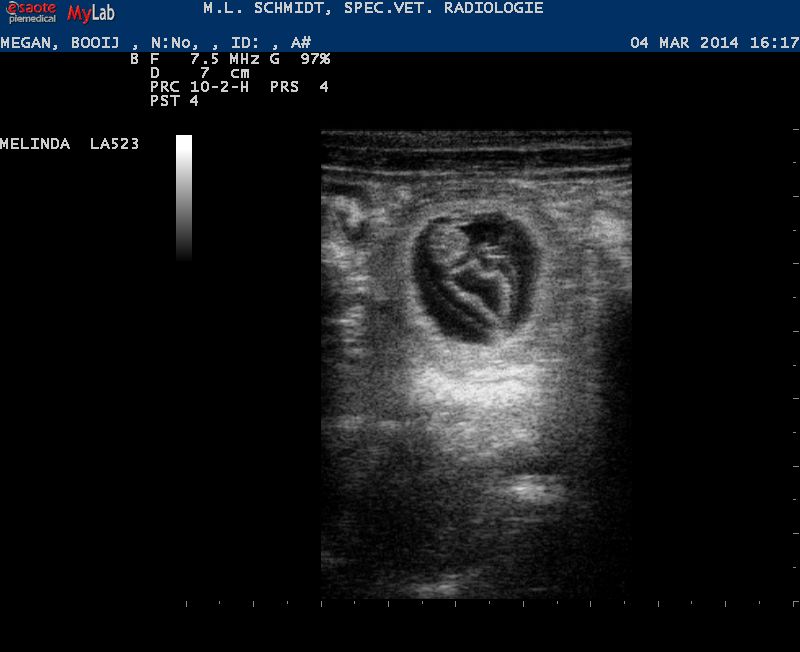

Volgende blog wordt het tijd voor een buikfoto van Megan. Want die dijt al lekker uit en heeft gelukkig volgens Marianne haar eetlust weer helemaal terug.